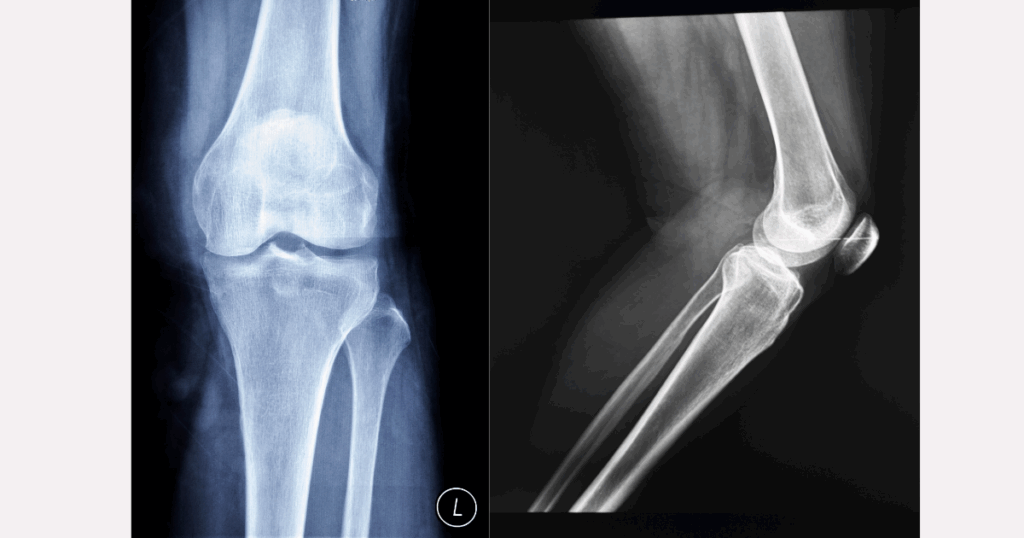

X-quang chỉ cho thấy xương – không hiển thị dây chằng

X-quang là một trong những phương tiện chẩn đoán hình ảnh phổ biến nhất trong cấp cứu chấn thương. Nó được sử dụng rộng rãi vì nhanh, chi phí thấp và đặc biệt hiệu quả trong việc phát hiện các tổn thương liên quan đến xương, như:

Tuy nhiên, giới hạn lớn nhất của X-quang nằm ở chỗ: nó không hiển thị được các mô mềm như dây chằng, sụn chêm, bao khớp hay cơ. Dây chằng chéo trước (ACL) là một cấu trúc mô mềm nằm sâu bên trong khớp gối, nên hoàn toàn “vô hình” trên phim X-quang. Vì vậy, ngay cả khi ACL đã bị rách hoặc đứt hoàn toàn, phim X-quang vẫn có thể cho hình ảnh hoàn toàn bình thường. Không có dấu hiệu gãy xương cũng không có nghĩa là khớp gối đang ổn. Nếu chỉ dựa vào X-quang mà bỏ qua các dấu hiệu lâm sàng điển hình, nguy cơ bỏ sót chẩn đoán là rất lớn.